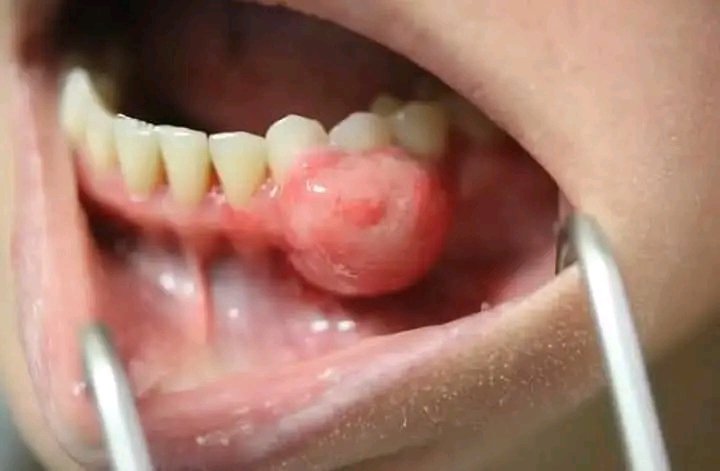

Symptoms of gum abscess include swollen, red, and painful gums, bleeding while brushing or flossing, bad breath, pus discharge, and sensitivity near the gum line. You may also notice gum recession, loose teeth, and a bad taste in the mouth. Immediate dental care is advised to prevent worsening infection.